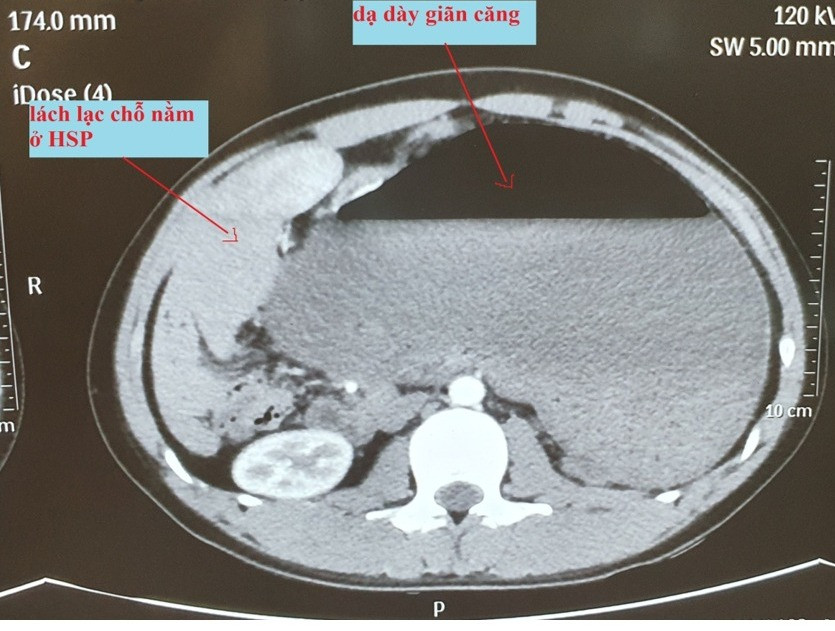

Hình ảnh cắt lớp vi tính (CT) cho thấy dạ dày giãn căng, lách lạc chỗ nằm vị trí hạ sườn phải ngay dưới gan, thận trái lạc chỗ nằm ở hố lách. Bệnh nhân được chẩn đoán xoắn dạ dày. Ngay lập tức, bệnh nhân được đặt sonde dạ dày, hút ra được khoảng 4 lít dịch tiêu hóa lẫn thức ăn; bù dịch, điện giải.

Tiến sĩ Nguyễn Trọng Hòe, khoa Ống tiêu hóa, cho biết khi mổ cấp cứu, bác sĩ thấy dạ dày tự xoắn 180 độ theo trục mạc treo, cùng chiều kim đồng hồ, giãn căng, kéo theo lách sang vị trí hạ sườn phải. Bác sĩ cũng phát hiện bệnh nhân có bất thường giải phẫu cơ hoành, vùng cơ hoành trái phía trên hố lách dị dạng tạo thành một hốc lớn ở phía sau, thận trái lạc chỗ nằm ở hốc này.